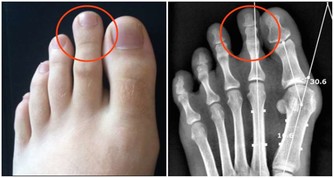

8.鎂:維持骨骼強壯、調節心律、增強免疫力

日推薦量:男性---420毫克,女性---320毫克。

食物來源:全穀類、堅果、綠色蔬菜。

特別提醒:富含鎂的食物有助於預防2型糖尿病,也可能會降低女性得高血壓的風險。